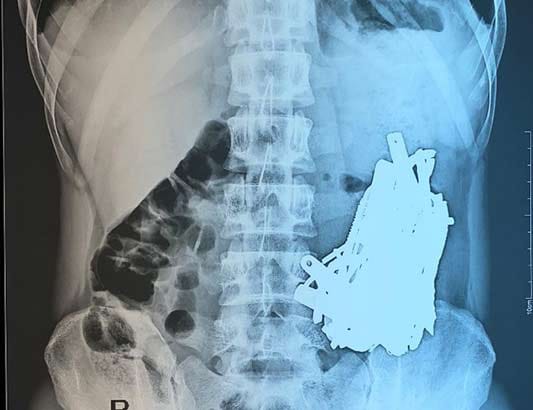

Bác sĩ 'choáng' khi phát hiện vô số đinh, thìa, lưỡi dao trong bụng nam bệnh nhân